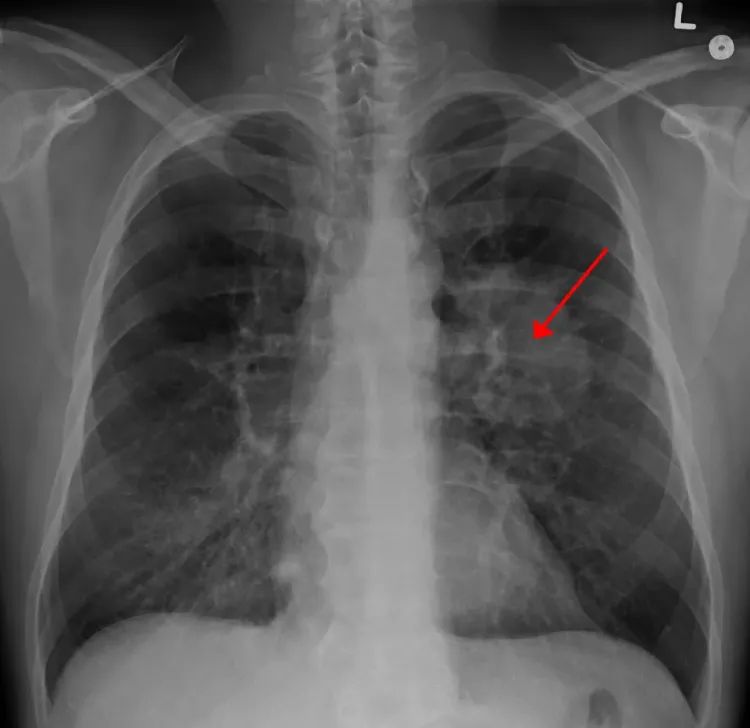

Coronavirusul nu lasă leziuni la nivelul plămânilor

Virusologul clujean Molnar Geza, profesor la UMF Cluj, a spus că cercetările făcute nu au arătat că virusul COVID 19 ar putea lăsa leziuni la nivelul plămânilor.

Infecția cu coronavirus nu lasă leziuni în timp, nu lasă leziuni, dar poate accentua leziunile la persoanele care au bronhopneumopatii cronice, obstructive, bronșite cronice, repetate infecții pulmonare, care sunt de altfel pe un plămân deja atins, lezat, prin boala cronică. Repet, nu am cunoștințe de date științifice că lasă sechele iremediabile, nevindecabile, până la ora actuală. În genere, virozele respiratorii se vindecă”, a declarat virusologul Molnar Geza.